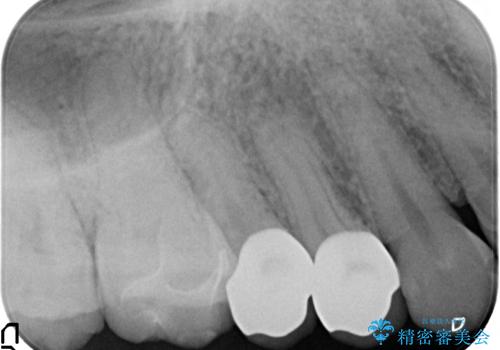

- 右上の銀歯を白くしたいといらっしゃった方の症例です。

右上4、5番目の歯はオールセラミッククラウンによる補綴、6番目の歯はセラミックインレーによる修復を行いました。